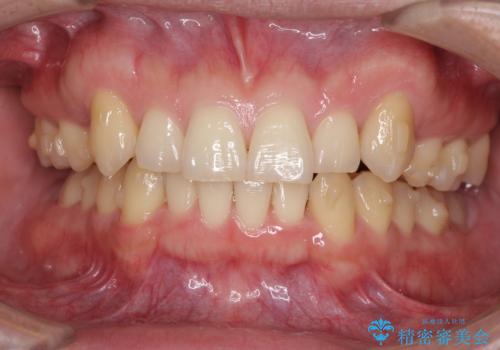

- 上顎の八重歯と前歯のデコボコを気にして来院された患者様です。

八重歯の移動量が多く、インビザライン単体での治療は困難と判断し、補助装置により八重歯移動後にインビザラインを用いることとしました。

治療途中で遠方に転勤となったため、通院が困難となり治療期間が長期化してしまいました。

上顎のみの抜歯矯正をインビザラインで行う場合、奥歯の前方移動がインビザラインでは苦手のため、奥歯の咬み合わせが不十分となることがあります。

今回の治療では終了時に奥歯は接触しているものの、接触の程度は物足りないものがある状態でした。今後保定期間に少しずつ奥歯の咬合を改善させていくことになります。